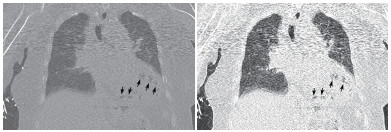

患者女性,75岁。因“被发现晕倒在地伴大小便失禁6 h余”于2018年10月25日12:10入院。患者为独居老人,当晚失联,入院6 h前,家人在家中发现其神志不清,大小便失禁,卧于床边,后患者家属呼120送至本院急诊科。入院后详细追问病史,患者身边无药瓶,家中亦无煤烟味。既往有“冠心病陈旧性心肌梗死、高血压病、2型糖尿病”病史11年余,“卵巢癌术后放化疗”病史2年余,“直肠占位”病史半年余。入院急诊体格检查:体温36.0℃,脉搏80次/min,呼吸17次/min,血压108/52 mmHg(1 mmHg=0.133 kPa),老年女性,神志不清,烦躁,面色苍白,皮肤湿冷、散在花斑,皮肤黏膜无破损。双侧瞳孔等大等圆,对光反射存在,言语、伸舌及肌力检查不合作,双肺呼吸音清,未闻及干湿性啰音,心率80次/min,律齐,心脏各瓣膜听诊区未闻及杂音,肝脾肋下未及,双下肢无水肿,四肢可见不自主活动,双侧病理征未引出。入院后心电图提示肢体导联及胸导联均有T波低平或倒置,V4-V6导联ST段压低(图 1)。血常规:白细胞计数32.35×109/L,中性粒细胞比率84.7%,中性粒细胞计数27.4×109/L,血红蛋白64 g/L,血小板计数221×109/L;CRP 111.9 mg/L,PCT > 100 ng/mL;肌酸激酶1 847 U/L,肌酸激酶同工酶356 U/L,肌酐219 μmol/L,肌钙蛋白T 6 257 pg/mL,NT-proBNP > 35 000 pg/mL。入院后急查颅脑、胸部及全腹CT,胸部CT提示左心室、室间隔及肺动脉根部区域见不规则条状、条片状低密度影,参考CT值约-200~-900 HU(气体密度影),外周伴伪影,左心室为著,外周分布为主,似累及心肌区域,部分心肌变薄,心包区域尚连续,主动脉系统未见气体影(图 2~3)。12:45患者病情急剧进展,呼吸心搏骤停,予气管插管、心肺复苏及药物抢救治疗,13:25抢救无效临床死亡,患者家属拒绝尸检。

| 示左心室、室间隔见不规则条状、条片状低密度影,参考CT值约-200~-900 HU,提示为气体影,左心室为著,外周分布为主,似累及心肌区域,部分心肌变薄,心包区域尚连续(白色箭头所示) 图 2 患者胸部CT结果 |

| 示气体影以左心室为著,外周分布为主,似累及心肌区域,部分心肌变薄(黑色箭头所示) 图 3 患者胸部CT冠状位影像 |

本例患者恶性肿瘤、糖尿病病史等使患者免疫功能低下,易合并重症急性感染。胸部CT显示左心室、室间隔及肺动脉根部区域见不规则条状、条片状低密度影,测量CT值提示为气体密度影。2016年Laiq等[1]曾报道因感染性心内膜炎致患者左心室内气体形成一例,患者血培养提示柠檬酸杆菌生长,最终患者发生急性心力衰竭,紧急二尖瓣置换术,术后乳头组织同样培养出柠檬酸杆菌,经抗感染治疗预后良好。2014年Alladina等[2]也曾报道一例因播散性肺克雷伯杆菌感染、产气,气体进入血液系统引起的脑空气栓塞。另外,临床工作中某些有创诊疗中,如深静脉置管、肺穿刺活检等也可能引起心脏空气栓塞[3-4]。但本例报道患者脑动脉、主动脉等大动脉系统未见明显气体影,说明患者左心室内气体不具有流动性。仔细观察胸部CT影像学表现,气体在左心室内主要沿室壁分布,部分心肌壁变薄,综合考虑为左室心内膜炎可能。左室内气体位于心内膜下,不在心腔内,故不具备游走性,这也就能解释为何患者其他动脉系统血管内不存在气体的原因。

本例患者存在重症急性感染,烦躁、皮肤湿冷、皮肤散在花斑,提示患者可能存在感染性休克,急性感染累及心内膜、心肌导致心内膜炎、心肌炎,细菌产气引起心内膜下气体形成。但遗憾的是,患者病情进展迅速,患者家属拒绝尸验,无法获得进一步临床资料。死亡原因推测可能为感染性休克,加之感染侵蚀患者心内膜,心肌使心肌变薄,最终引起心脏破裂或心内膜下气体破入心腔内引起空气栓塞而死亡。